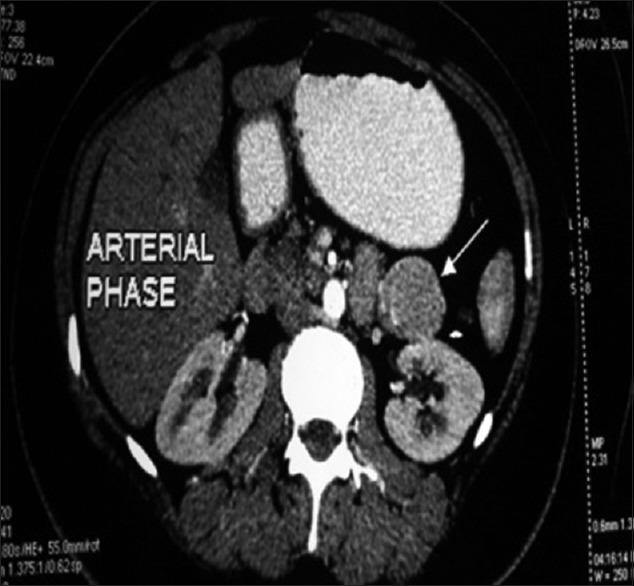

Castleman's disease (CD) is a rare disorder characterized by proliferation of the lymphoid tissue. Clinically, it presents in two forms either a unicentric (UC) or multicentric. Mediastinum is the most common location. UC retroperitoneal presentation is rare. We report a case of 29-year-old female who presented with left loin pain, and on abdominal imaging, evaluation identified a retroperitoneal mass in the left hypochondrium in the pararenal space. Mass was surgically excised entirely. Histopathological examination demonstrated hyaline vascular type of CD. CD should be considered in differential diagnosis of retroperitoneal mass, especially in equivocal cases. We also reviewed literature of 134 cases of retroperitoneal CD to analyze the presentation, management, and outcome.

卡斯特曼病(CD)是一种以淋巴组织增生为特征的罕见疾病。临床上,它表现为两种形式,即单中心型(UC)或多中心型。纵隔是最常见的发病部位。UC型腹膜后表现罕见。我们报告一例29岁女性,她因左腰部疼痛就诊,腹部影像学检查发现肾旁间隙左季肋部有一个腹膜后肿块。肿块被完整手术切除。组织病理学检查显示为透明血管型CD。在腹膜后肿块的鉴别诊断中应考虑CD,尤其是在不明确的病例中。我们还回顾了134例腹膜后CD的文献,以分析其表现、治疗和预后。